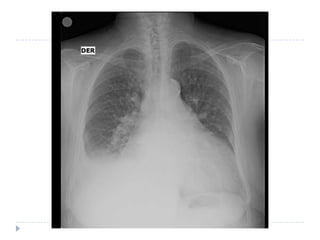

La radiografía de tórax

Cardiomegalia

 Redistribución venosa por

Guías deinsuficiencia cardíaca.

Estudio básico  En elelectrocardiograma,       Bloqueo AV de primer grado Bloqueo completo de rama izquierda Hemibloqueo anterior Alteraciones inespecíficas de conducción intraventricular. Fibrilación auricular. La radiografía de tórax Cardiomegalia  Redistribución venosa por Guías deinsuficiencia cardíaca. práctica clínica de la Sociedad Española de Cardiología en miocardiopatías y miocarditis Rev Esp  Cardiol 2000; 53: 360-393